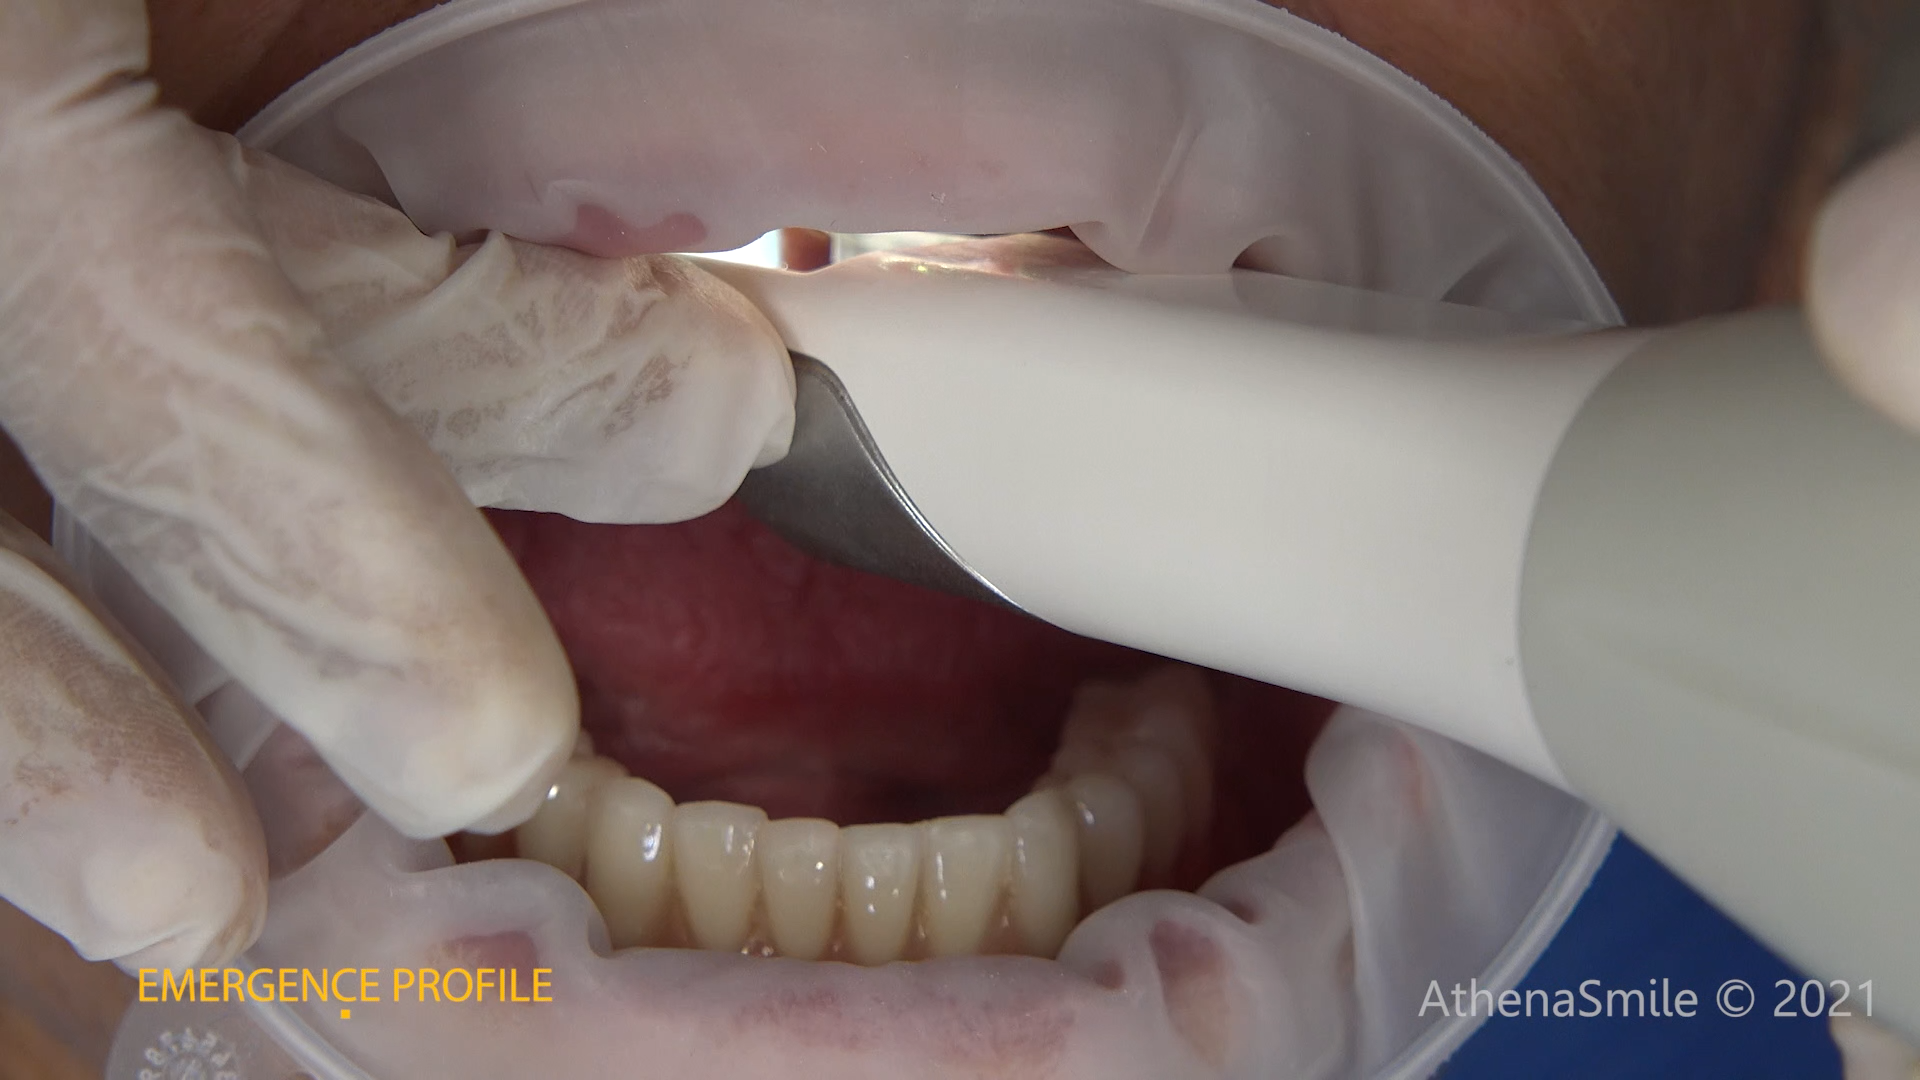

The use of CDP (Complete Digital Patient) as a basis for planning in a case of complete implant rehabilitation with a full arch in zirconia – ceramicised

Case study carried out with Athena Smile Pelekanos (GR ) : dott . Stavros Pelekanos